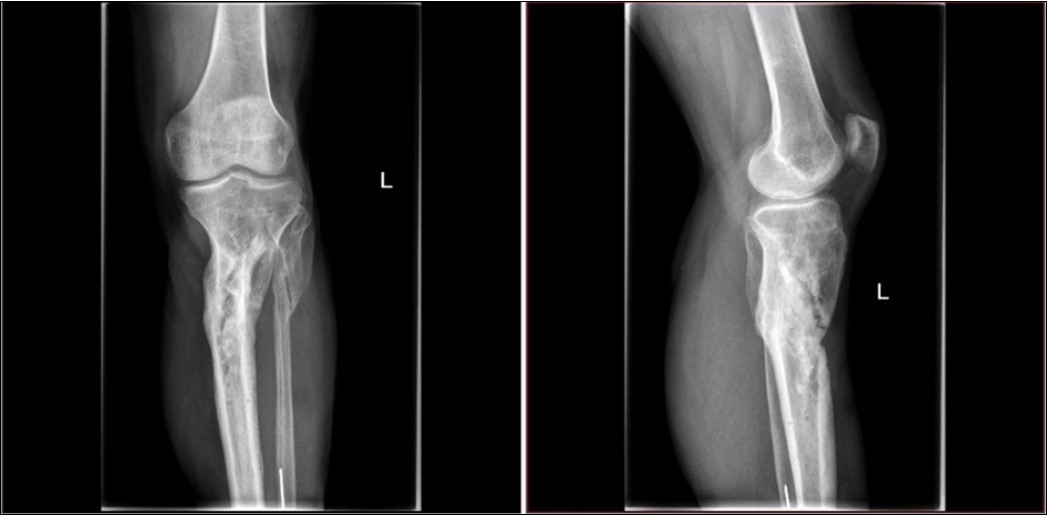

Figure 28.23 April. Surgery conversion of osteosynthesis. Removal external fixator and implantation intramedullary tibial nail. Gradual bone healing - last X-ray september 2019

Figure 29.23 April. Surgery conversion of osteosynthesis. Removal external fixator and implantation intramedullary tibial nail. Gradual bone healing - last X-ray september 2019

Figure 33. X-ray documentation of the whole treatment of tibia fracture. External fixation was used throughout the treatment until bone was healed. From 9.October 2015 to 2.February 2017